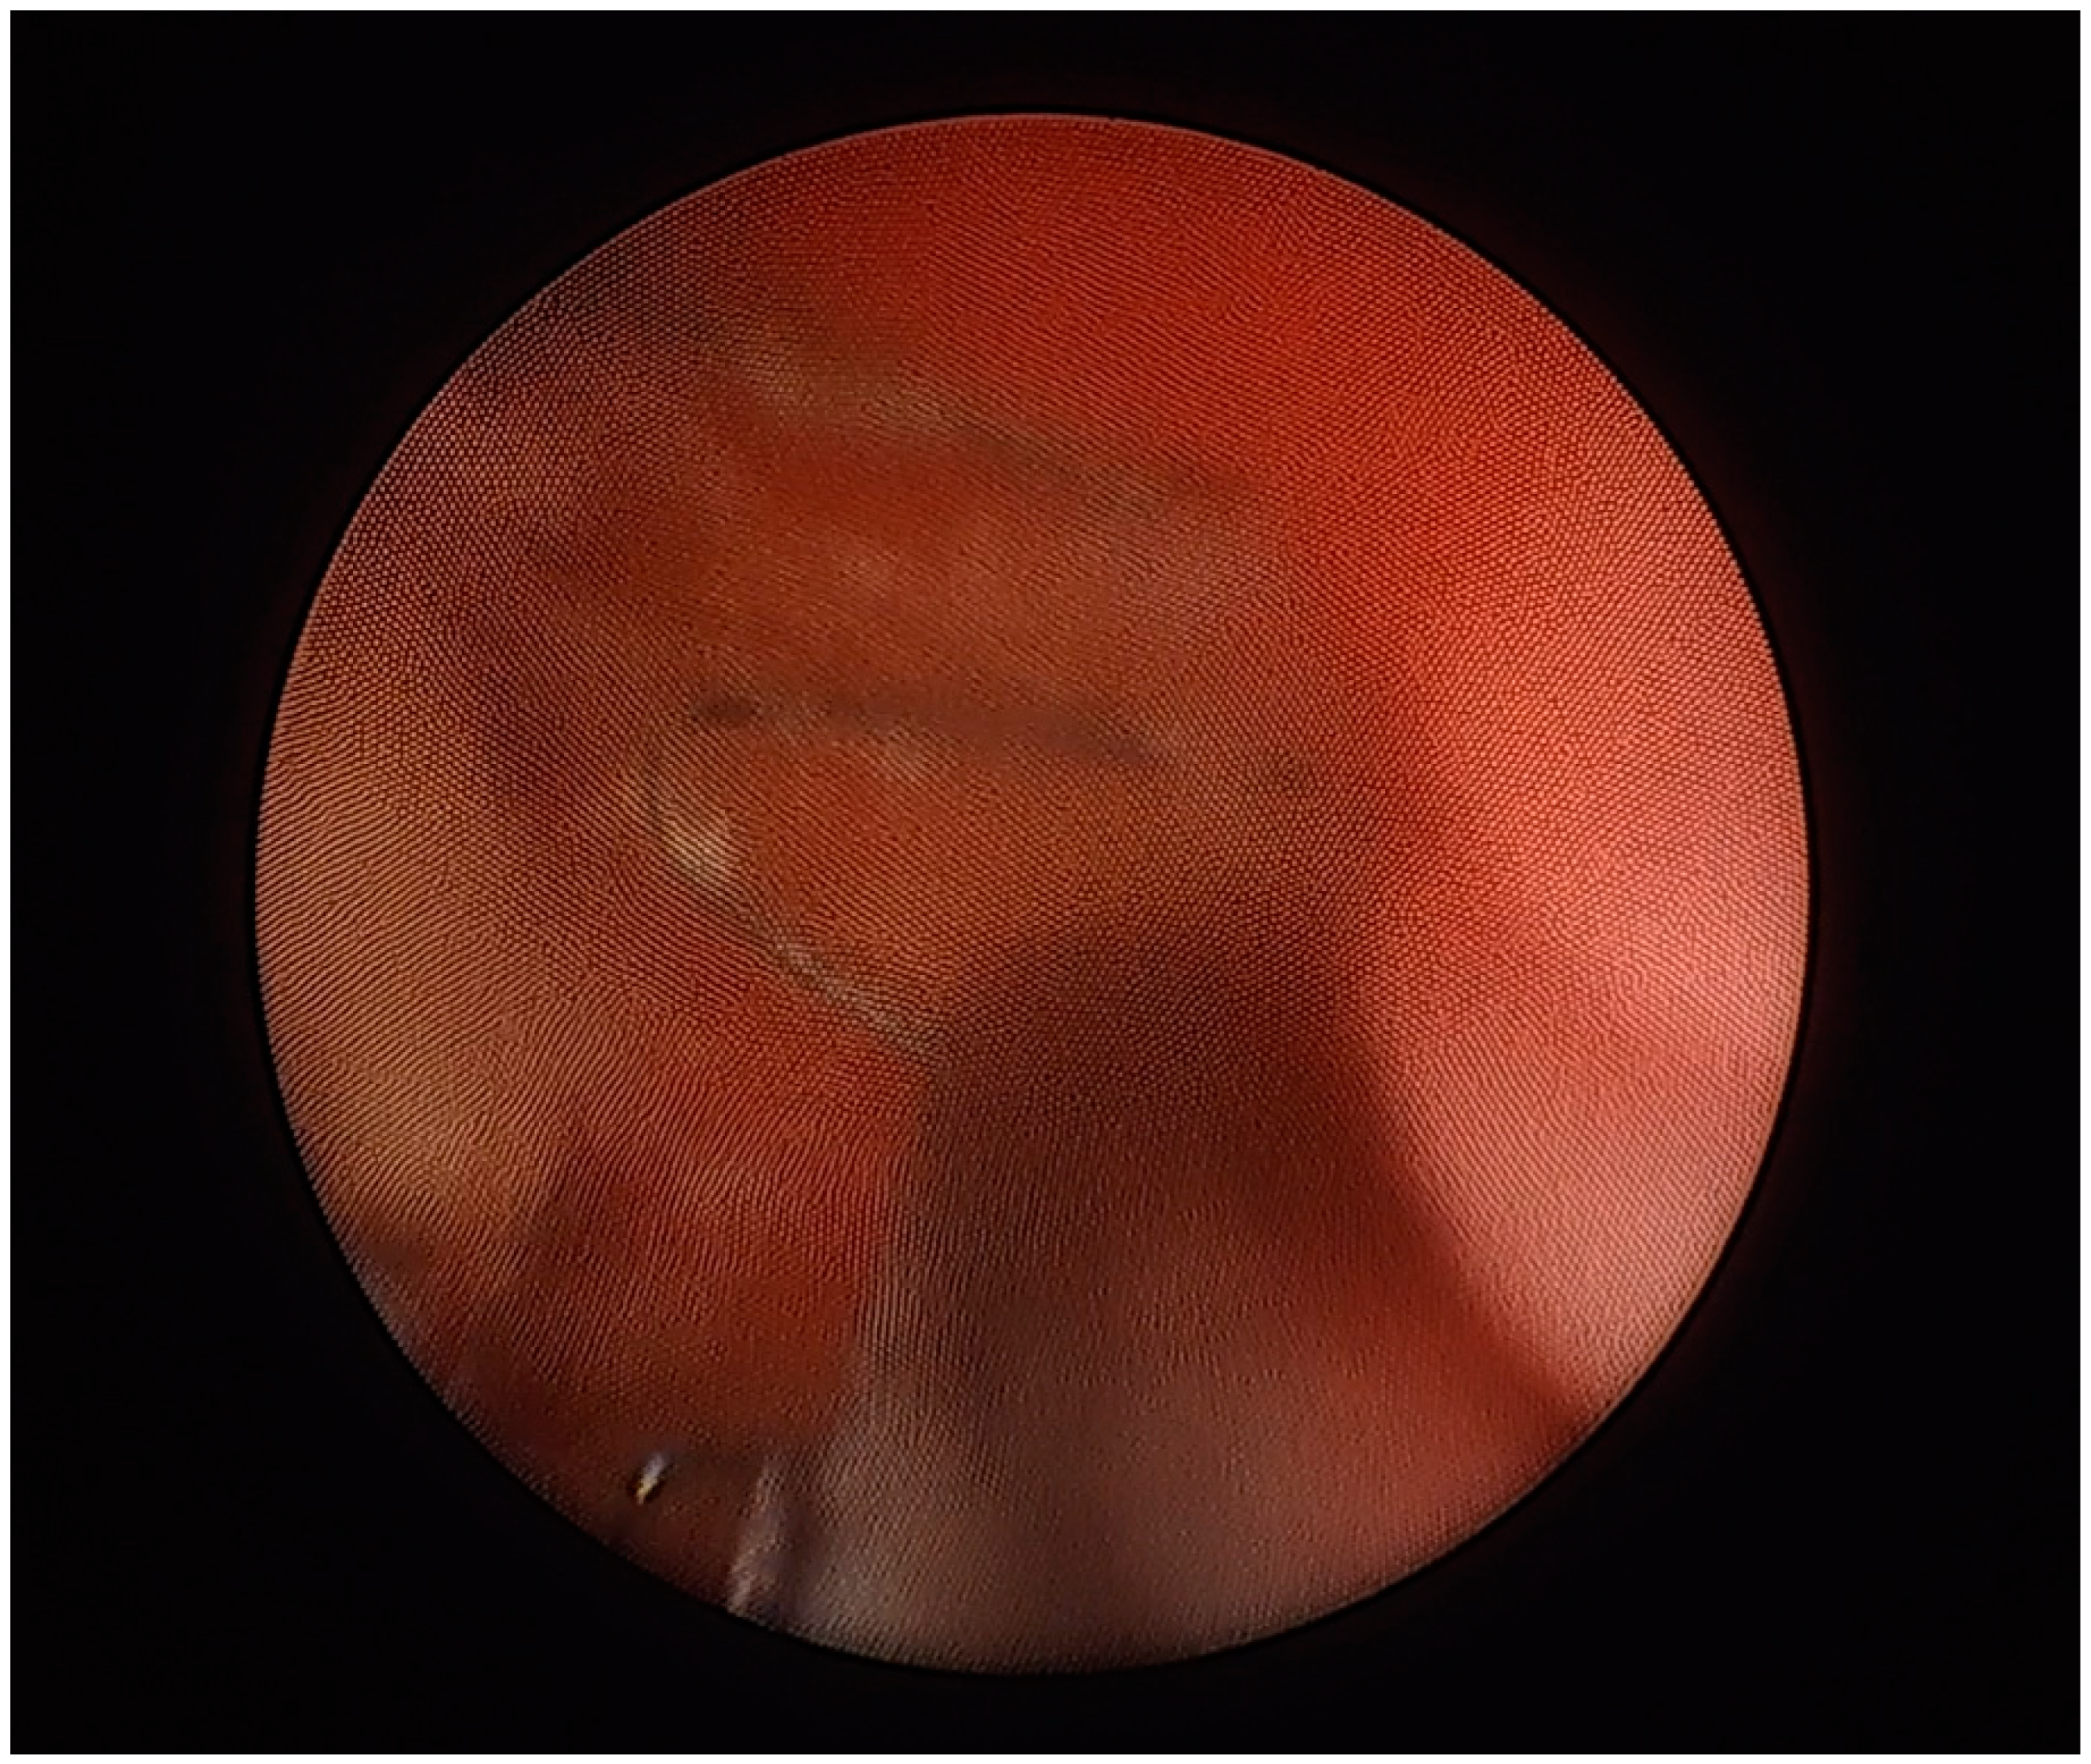

A circa 3 cm protruding fragment of the stent (Figure 4) was removed from the bladder lumen by means of a cystoscopy combined with a suprapubic bladder endoscopy. The procedure fully resolved the complaints previously reported by the patient. Her blood pressure remained within normal limits.

Figure 4.

A cystoscopic view of the ureteral stent protruding into the urinary bladder lumen. The stent was trimmed using simultaneous cystoscopic and suprapubic intravesical access (13 May 2022).